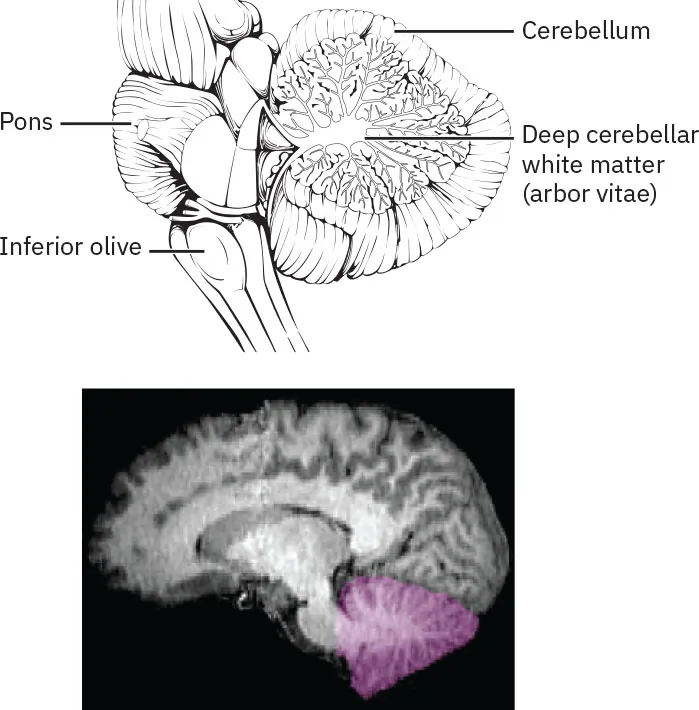

The cerebellum is the “little brain.” It is covered in gyri and sulci like the cerebrum and looks like a miniature version of that part of the brain (Figure 23.6). The cerebellum is largely responsible for comparing information from the cerebrum with sensory feedback from the periphery through the spinal cord. It accounts for approximately 10 percent of the mass of the brain (Van Essen et al., 2018).

The image contains two diagrams of the human brain focusing on the cerebellum. The top diagram is a detailed anatomical drawing showing a section of the brain with key structures labeled: the cerebellum located at the lower back part of the brain, the deep cerebellar white matter (arbor vitae) inside the cerebellum, the pons positioned above the cerebellum as part of the brainstem, and the inferior olive near the base of the brainstem, adjacent to the cerebellum. The bottom diagram is a sagittal MRI scan of the brain, highlighting the cerebellum in purple to emphasize its location and structure within the brain, while the rest of the brain appears in grayscale, providing contrast to the highlighted cerebellum.

Figure 23.6 The cerebellum is situated on the posterior surface of the brain stem. (credit: modification of work from Anatomy and Physiology 2e. attribution: Copyright Rice University, OpenStax, under CC BY 4.0 license)